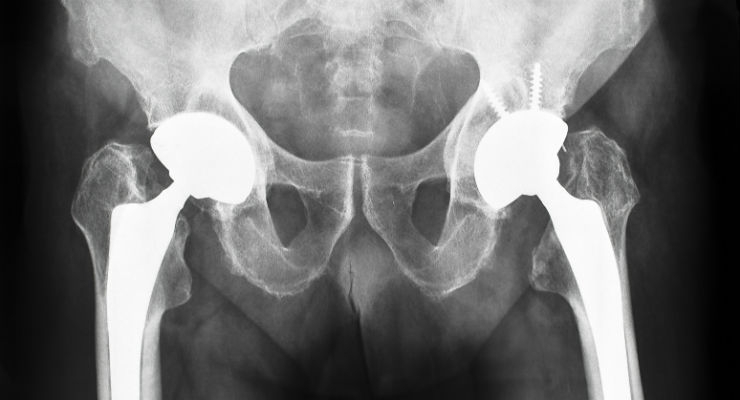

Выбор внутренней фиксации по сравнению с заменой сустава В настоящее время считается, что внутренняя фиксация полым стержнем при переломе шейки бедра имеет преимущества короткого времени операции, небольшой травмы и низкой стоимости, но у большинства пожилых пациентов наблюдается остеопороз, поэтому стабильность